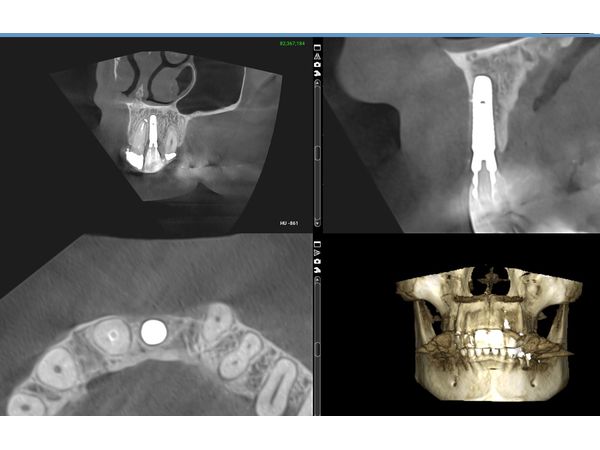

По результатам компьютерной томографии челюстей:

- атрофия и разрушение вестибулярной кортикальной пластинки;

- вертикальный перелом корня зуба.

По результатам повторной компьютерной номограммы, вестибулярная кортикальная пластинка и объём костной ткани восстановились. Пациентка ни на что не жаловалась. Внешний вид её полностью устроил.